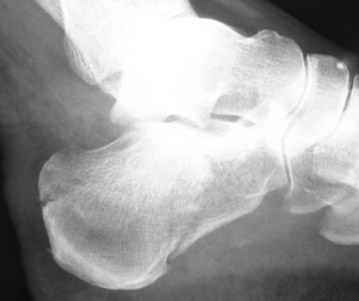

Une deuxième chance ?

Dr Jacques Fechtenbaum Hôpital Cochin - Paris

Le 03 novembre 2010, Mr F., 24 ans, s’est défenestré du 4ème étage.

Adressé en urgence dans un service d’orthopédie, la fracture du calcanéum a été ostéosynthésée.

La fracture de la vertèbre L1 a également été chirurgicalement immobilisée.

Quinze jours après, il marche normalement, sans boiterie, sans séquelle.